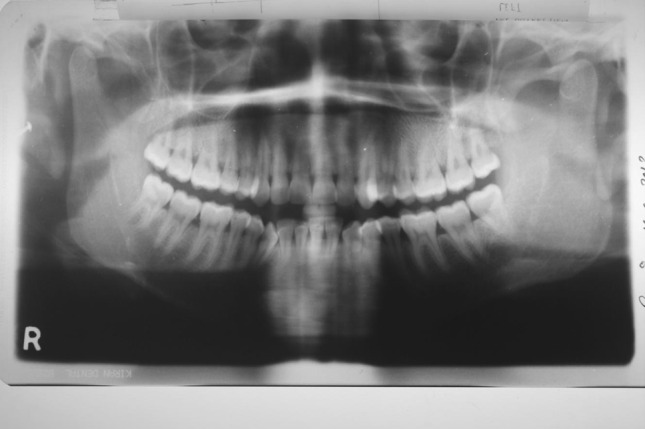

Fig. 13.

Pre-treatment OPG

Fig. 14.

Post-treatment OPG